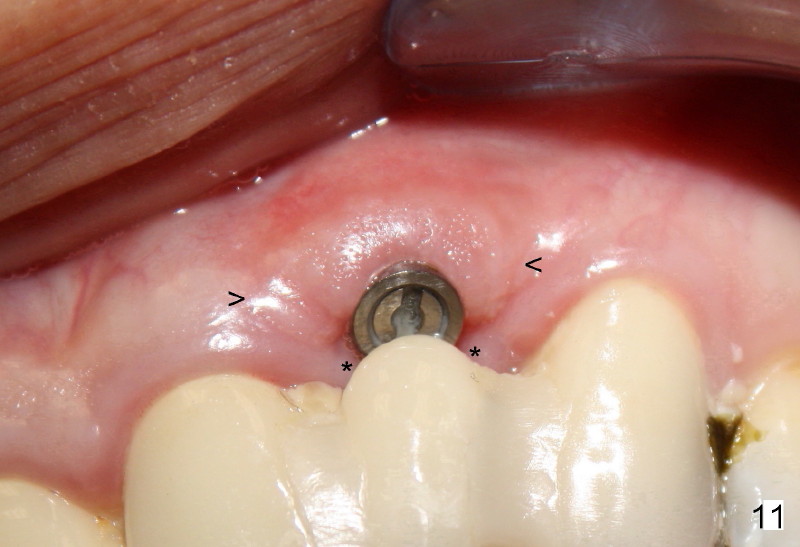

Segmental Osteotomy for Misplaced Implant

This corrective surgery was performed by Dr. Bernee Dunson.

Xin Wei, DDS, PhD, MS 1st edition 12/21/2011, last revision 12/23/2011